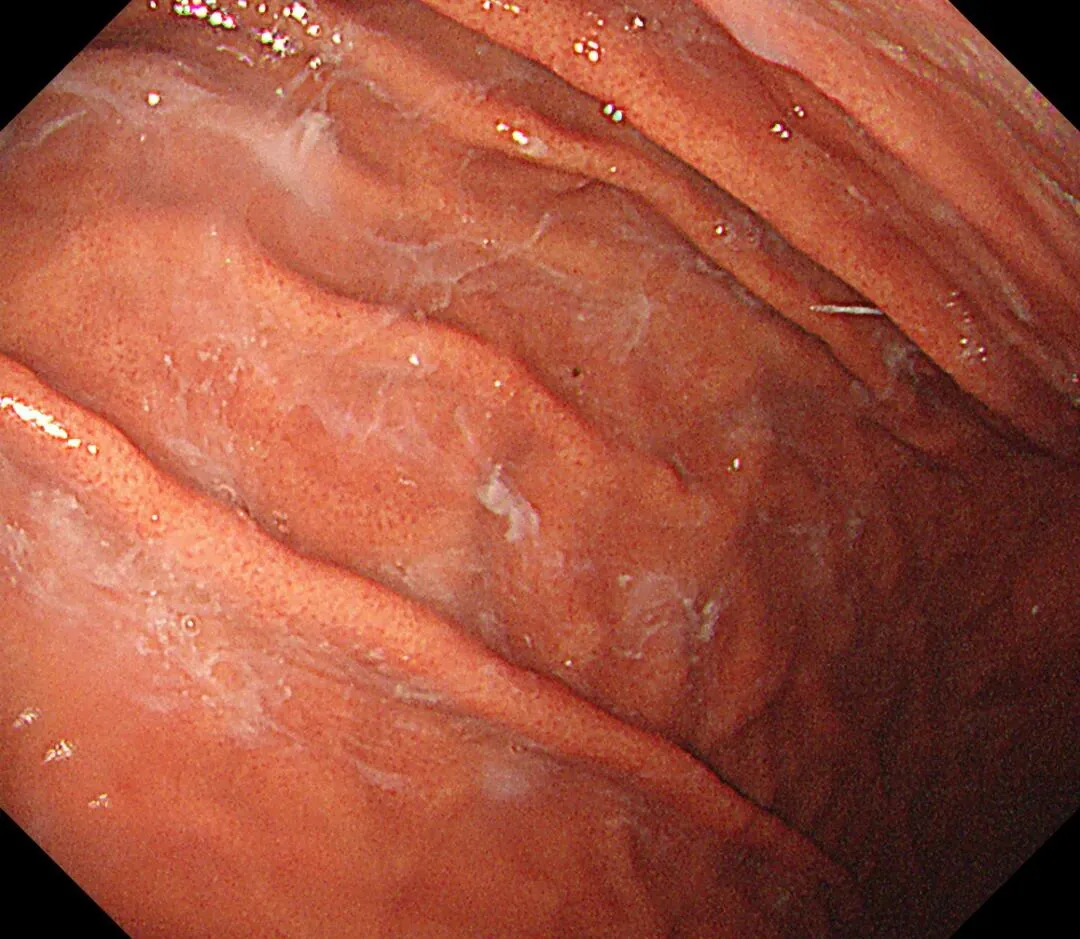

蛛网状黏液(web-like mucus):以胃底、胃体大弯为中心,有时可见白色透明、水洗难以去除的黏液附着,因外观与蜘蛛网相似而命名,多见于口服钾离子竞争性酸阻滞剂(P-CAB)患者,可能是因为其强效、持续抑酸作用所致,具体机制尚需进一步研究明确。

蛛网状黏液case1,服用P-CAB药物(具体服用时长不详)👇

个人体会:蛛网状黏液与P-CAB药物相关,顽固性黏液与AIG相关,两种胃内环境都一样是胃酸缺乏,据说胃内PH升高可导致蛋白质变性形成“乳状”黏附,也据说是因为胃酸缺乏导致化生的黏液分泌细胞大量增多,分泌异常成分的高粘稠度黏液,两者的形成机制和内镜表现是比较类似的,不同之处在于蛛网状黏液除了比较“网状”之外,还比较“拉丝”、“乳白”,顽固性黏液比较“果冻”、“淡白”、"广泛涂层"、“紧贴大地”。。。词穷了,从小没学过语文课,还需多看书、观察更多病例加以总结,请各位老师们指正。。。